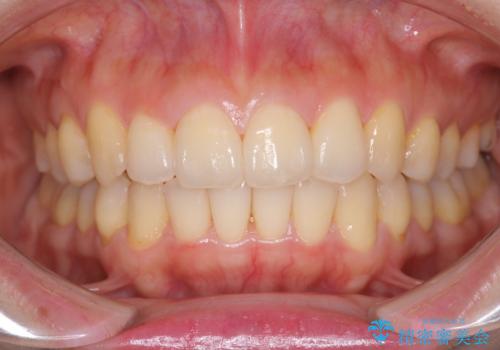

前歯が前後反対にかんでいる インビザラインによる目立たない矯正

歯と歯の間をわずかに削り、ガタガタを改善しました。

目立たずに矯正を終えることができて、喜んでいただけました。